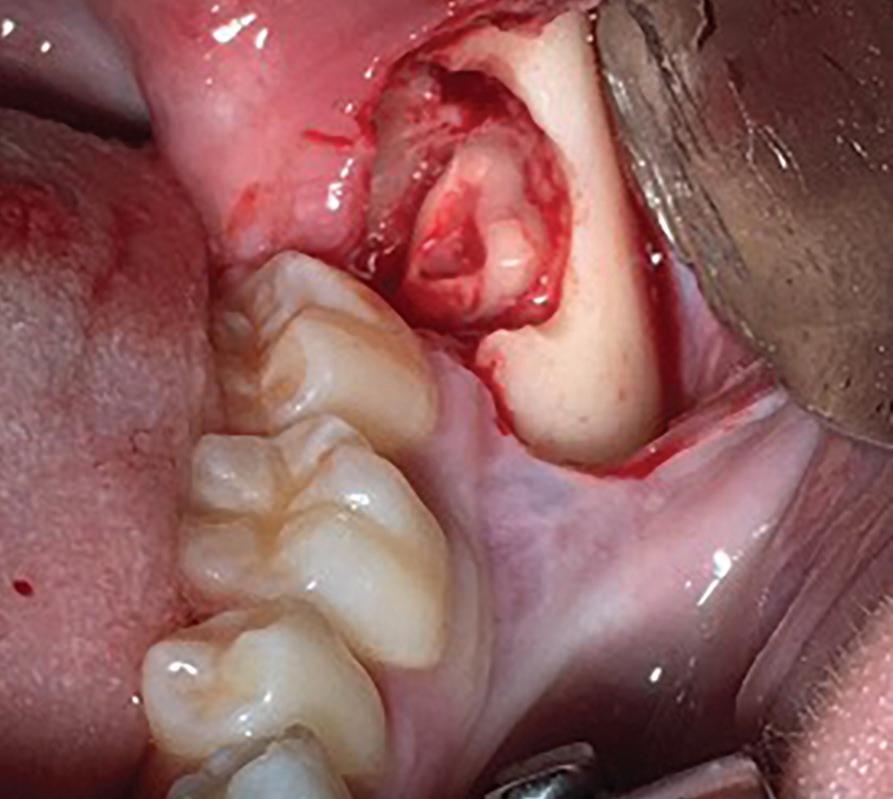

54 Oral and Maxillofacial Surgery

Root migration after coronectomy of impacted mandibular third molars: case reports